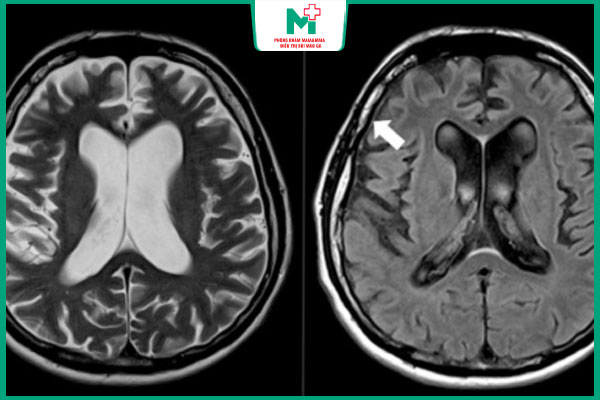

- Gây tổn thương nghiêm trọng và không thể phục hồi ở các cơ quan nội tạng, phát triển thành giang mai thần kinh hoặc giang mai tim mạch; ảnh hưởng tới não, van tim, có thể dẫn đến tử vong.